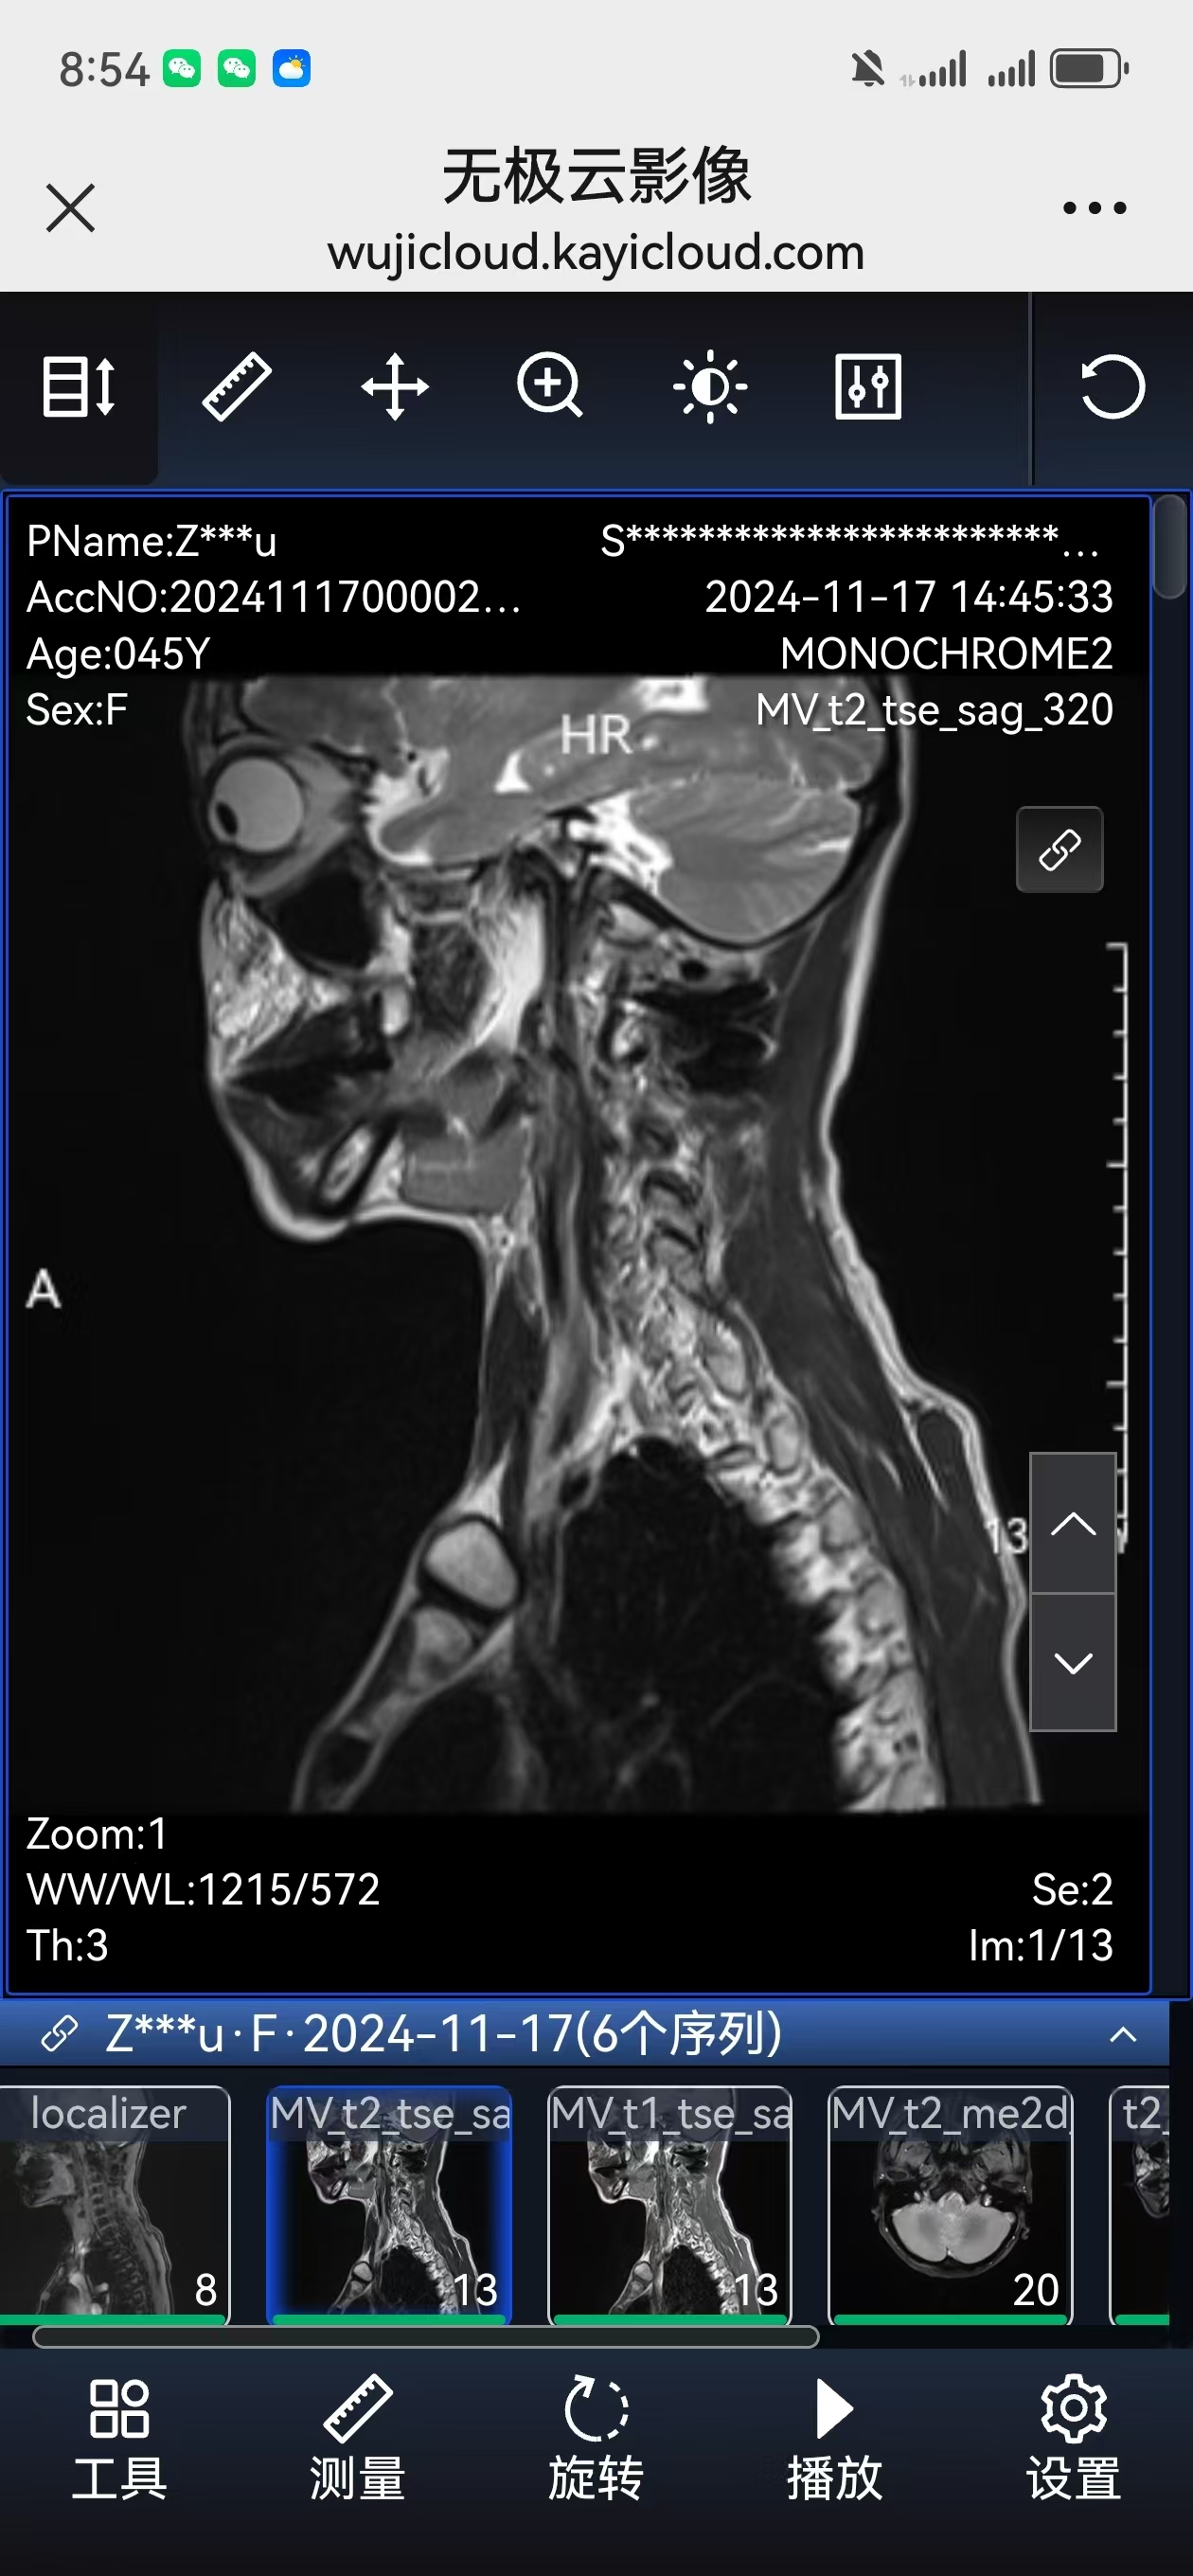

• 术后影像:

• 2024.11.07,复查,对位良好。